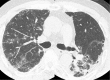

Varicella zoster virus (VZV) infection does not always provide lifelong immunity. A reinfection with VZV occurs more commonly than previously thought. Varicella infection spreads through the blood-stream, causing pneumonia. Varicella pneumonia results in bilateral pulmonary nodular infiltrations. We herein report a case of varicella reinfection with unilateral varicella pneumonia in which a reduced pulmonary blood flow due to radiation damage was considered to be the cause of unilateral pneumonia. In patients with an asymmetric pulmonary blood flow, careful interpretation of unilateral infiltration is therefore considered to be important with making a differential diagnosis.